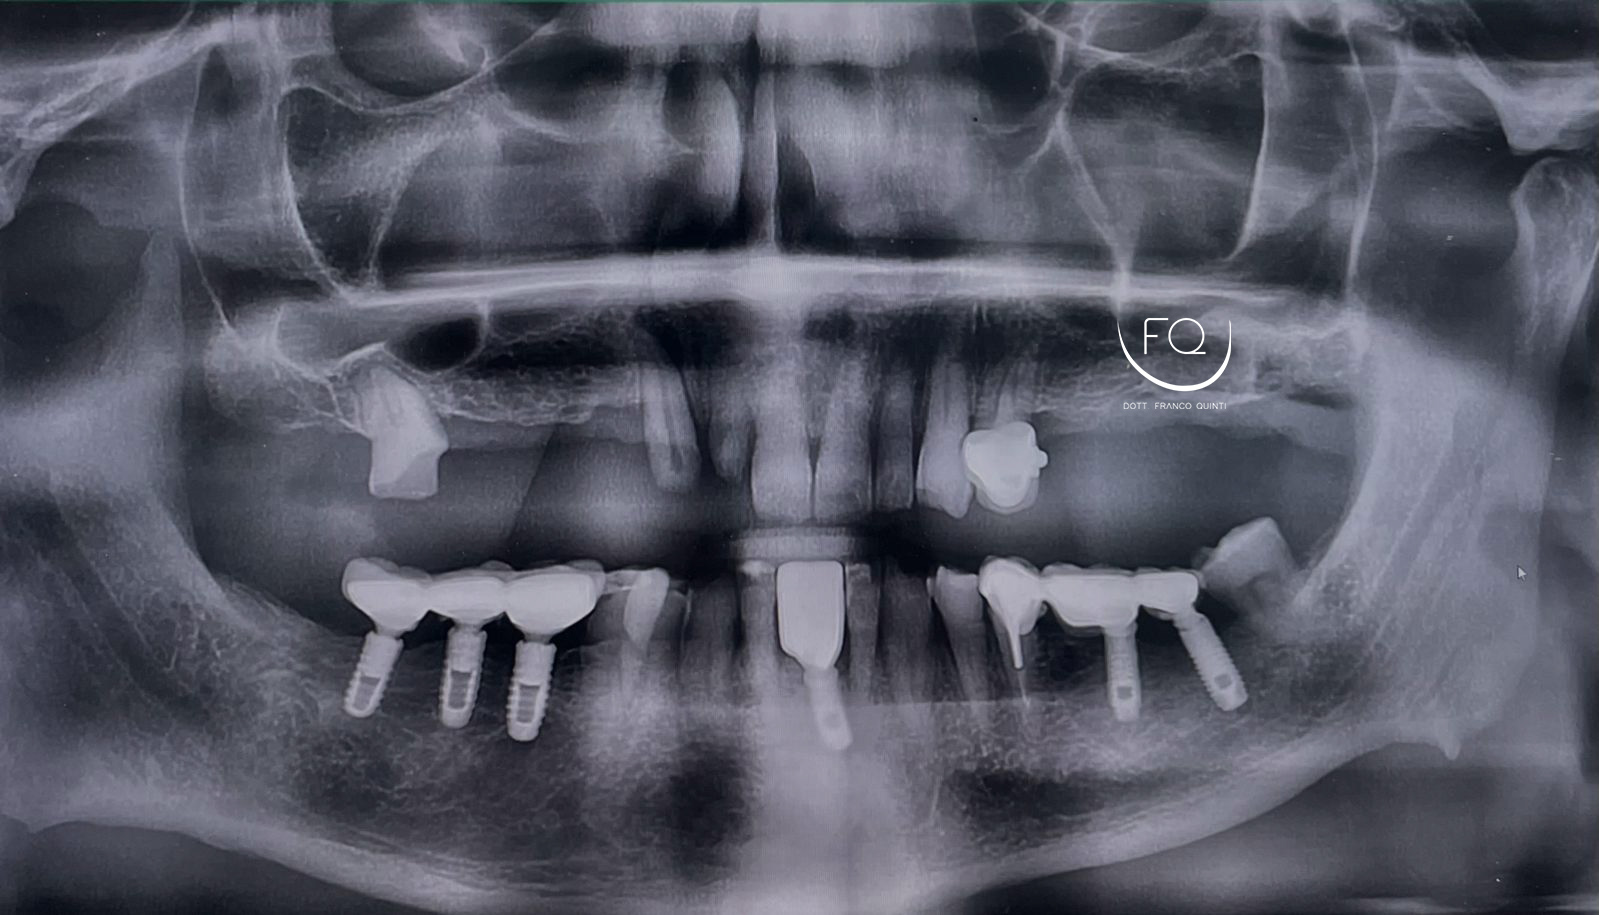

Questa settimana vi presento un caso di chirurgia computer guidata dell’arcata superiore realizzata con dima scomponibile doppia.

Nell’intervento sono stati inseriti 6 impianti PRAMA di Sweden & Martina con contestuale esecuzione del carico immediato.